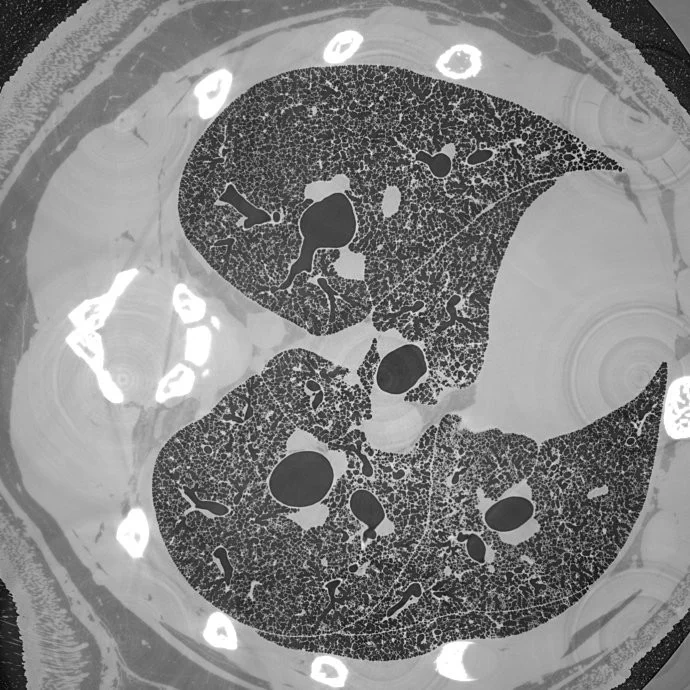

High-resolution cross-section throught the full lung of a freshly post mortem juvenile rat.

An international team of researchers, headed by the TOMCAT group and collaboration partners at the University of Bern, have used this method to acquire micrometer-scale resolution datasets on the entire lung structure of a juvenile rat in its fresh natural state within the animal’s body and without the need for any fixation, staining or other alteration that would affect the observed structure. The study is published as part of an upcoming special issue of Histochemistry and Cell Biology devoted to the topic of 3D lung imaging. The openly accessible 1.2 TB-sized dataset reveals the smallest structural features of the lung, the alveoli, over the whole extent of the lung.